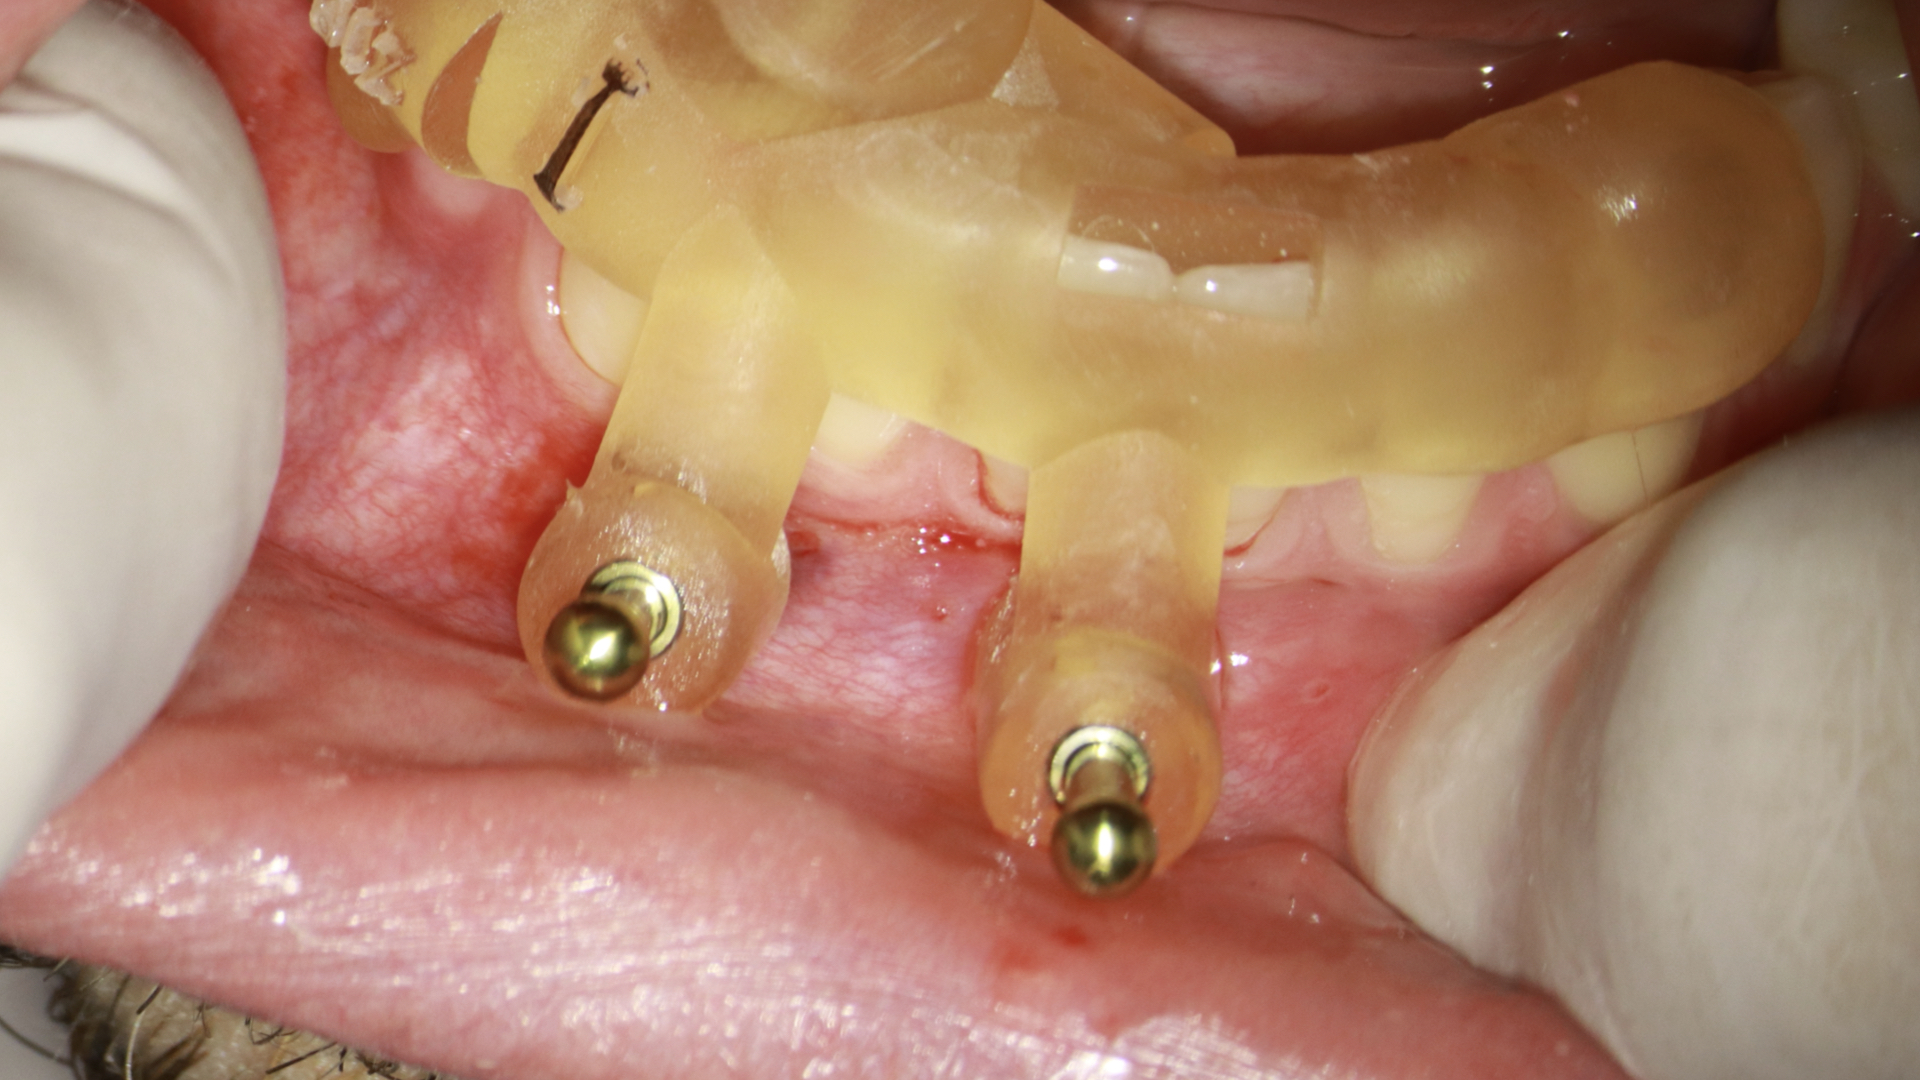

- Fixar o endoguide na arcada que necessita de tratamento com os fixadores. Estas anilhas usadas para a colocação da fresa e fixadores são metálicas. Para fazer está fixação é necessário o uso da fresa em osso. Você pode usar um motor endodôntico na máxima rotação e torque irrigando durante o procedimento ou um motor de implante que já tem a irrigação acoplada e facilita esta perfuração. A vantagem do motor de implante é que você consegue fazer a perfuração em osso com maior torque, o que possibilita que em caso de perfuração em mandíbula, com osso mais compacto, tenhamos um procedimento mais tranquilo (figura 7, 8 e 9).